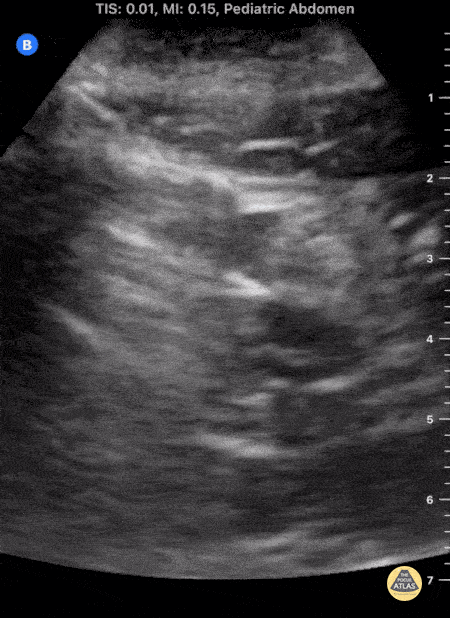

Teenage male presenting with abdominal pain worsening over 24 hours, diagnosed with acute appendicitis via POCUS. The clip shows a circular structure which measures at 6.5 mm transversely, representing an acutely inflamed appendix with surrounding anechoic free fluid. POCUS Acute Appendicitis: noncompressible, diameter >6mm, single wall >3mm are direct signs of appendicitis. Use of POCUS for diagnosis of acute appendicits significantly reduces cost and radiation exposure for patients without sacrificing diagnostic accuracy. Mostbeck, G., Adam, E.J., Nielsen, M.B. et al. How to diagnose acute appendicitis: ultrasound first. Insights Imaging 7, 255–263 (2016). Contributor: C. Malcolm Roberson, MD. @ProjectUltraEM